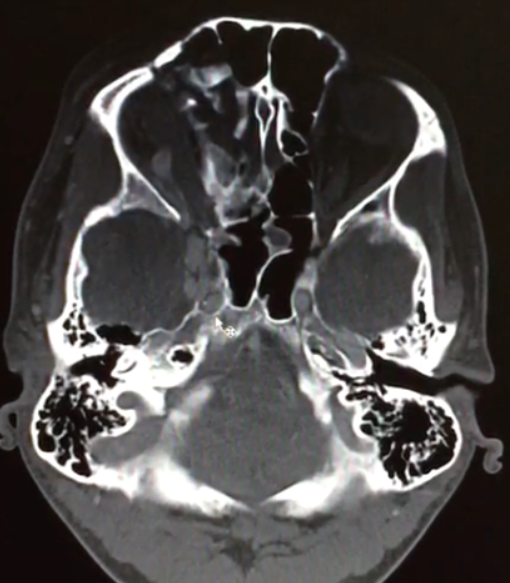

- Tomografia de crânio estrutura captante com a invasão de contraste. Ausência de coleção purulenta e presença de lesão em topografia de seio cavernoso e evidência da veia oftálmica superior. Além disso, a TC mostra sinais de traumatismo prévio (fratura frontal).

As fístulas arteriovenosas (FAVs) da região do seio cavernoso (SC) são lesões raras e difíceis de diagnosticar. Os principais sinais e sintomas são proptose, hiperemia conjuntival, quemose, paralisia dos III, IV, V e VI nervos cranianos, ptose palpebral, glaucoma, redução da acuidade visual e cefaleia. Nas fístulas carótido-cavernosa existe um defeito na parede da artéria carótida interna (ACI) que a comunica diretamente com o SC e, em consequência, um shunt arteriovenoso de grande volume. Na TC podemos identificar dilatação ou trombose da veia oftálmica superior (VOS), proptose, contrastação precoce do SC, espessamento da musculatura extraocular e edema da gordura periorbitária3.

As FCC diretas apresentam na maioria dos casos um alto débito ao contrário das FCC indiretas que em termos hemodinâmicos são de baixo débito. Etiologicamente as primeiras são traumáticas em cerca de 75% dos casos podendo, no entanto, ocorrer espontaneamente. As FCC indiretas são geralmente espontâneas, ocorrendo classicamente em mulheres pós-menopáusicas ou em grávidas. O diagnóstico é efetuado pela clínica e por Tomografia Computadorizada de crânio e/ou Ressonância Magnética Nuclear das Órbitas, onde o sinal mais específico é a dilatação da veia oftálmica superior. No entanto, o diagnóstico definitivo, a caracterização da fístula e o planejamento do tratamento endovascular só são possíveis com a angiografia cerebral6.